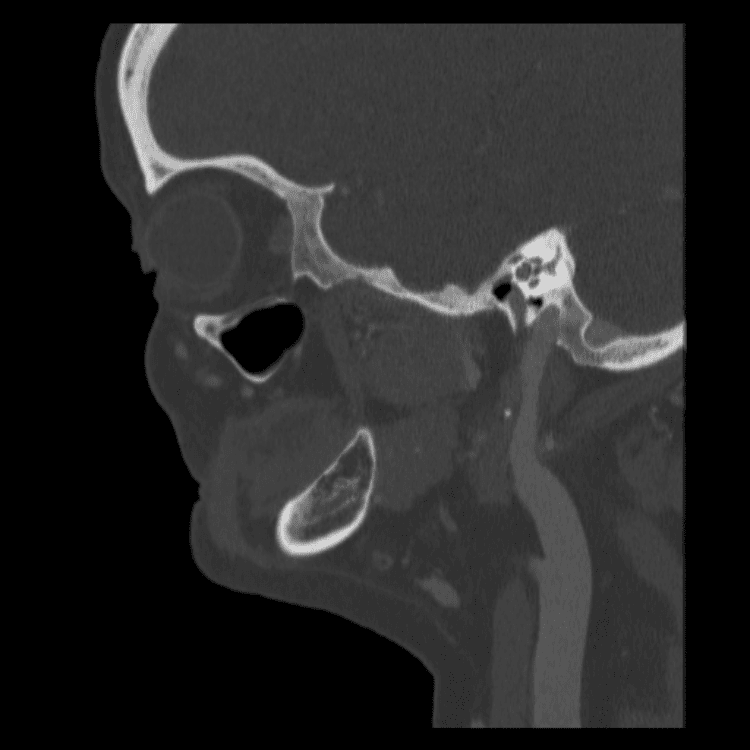

Head and Neck

Practice

Simulates call by including subtle or difficult cases and some normals.

27 cases